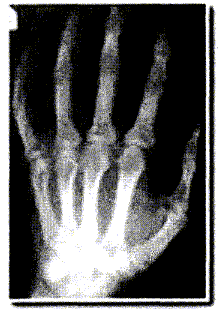

La radiographie enregistre l'image d'un corps traversé par un faisceau de rayons X. Suivant la constitution du corps, les rayons X sont plus ou moins absorbés et le film photographique, placé derrière le corps radiographié, est ainsi plus ou moins impressionné. Le document ci-dessous correspond à la radiographie d'une main. La main placée contre la plaque sensible s'intercale entre la source de rayons X et la plaque.

Les éléments calcium ( Z=20) et phosphore ( Z= 15) sont particulièrement présents dans les os.

Les éléments carbone (Z=6), hydrogène ( Z=1) et oxygène ( Z=16) sont les principaux éléments constitutifs des tissus.

En raisonnant sur les os et les tissus de la main, répondre aux questions suivantes :

- Quelle partie de la main a absorbé le plus de rayons X ? Justifier.

- Connaissant les éléments chimiques présents dans les os et dans les tissus, donner une explication possible justifiant la différence d'absorption qui apparaît sur la radiographie.

Lorsque l'absorption est importante, ( une grande partie des rayonx X est arrêté ), peu de rayons atteignent le film : le film est peu impressionné. ( teinte blanche)

Lorsqu'il n'y a aucune absorption ( en dehors de la main par exemple ) , tous les rayons X atteignent le film et l'impressionnent ( teinte noire).

Lorsque l'absorption est faible, ( une petite partie des rayonx X est arrêté ), beaucoup de rayons atteignent le film : le film est assez impressionné. ( teinte grise)

Les os absorbent fortemment les rayons X et apparaissent en blanc.

Les tissus absorbent peu les rayons X et apparaissent en gris.

L'absorption des rayons X est d'autant plus importante que le n° atomique de l'élément chimique est grand.